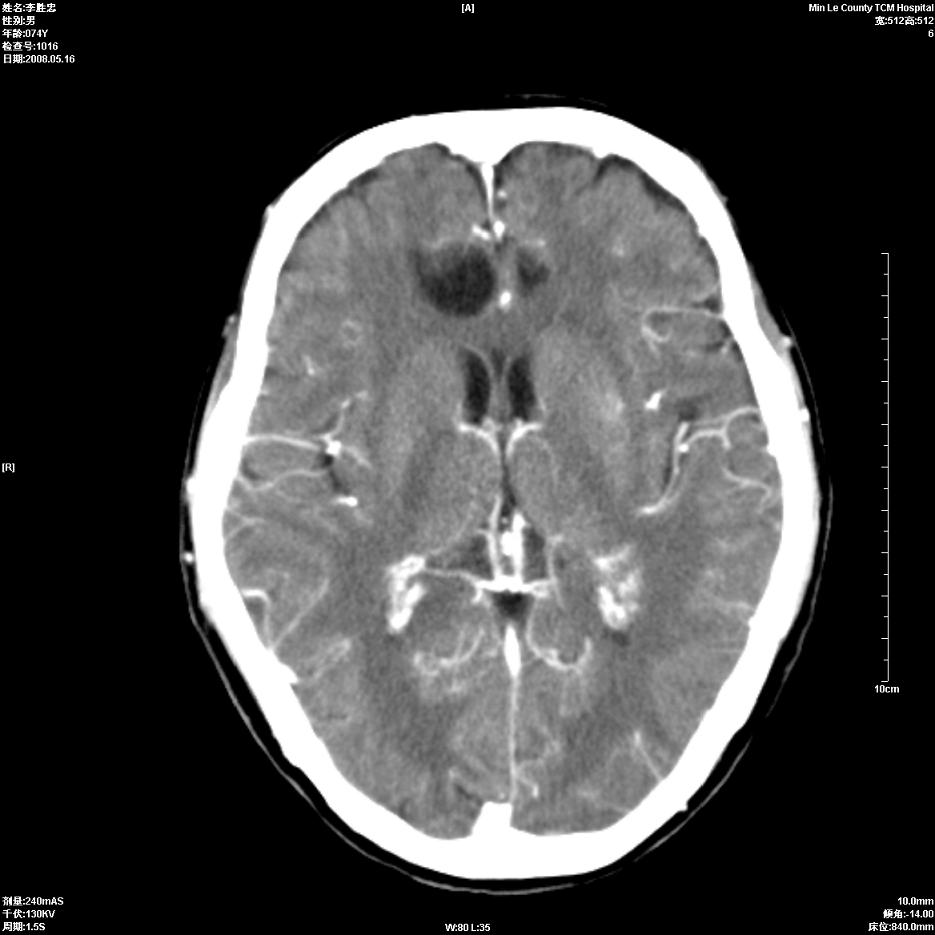

以下是引用hhcckk在2008-5-30 14:26:00的发言:[br]病灶跨中线,有占位效应,强化不明显,考虑胼胝体区低级别的星形细胞瘤可能性大,建议mr检查